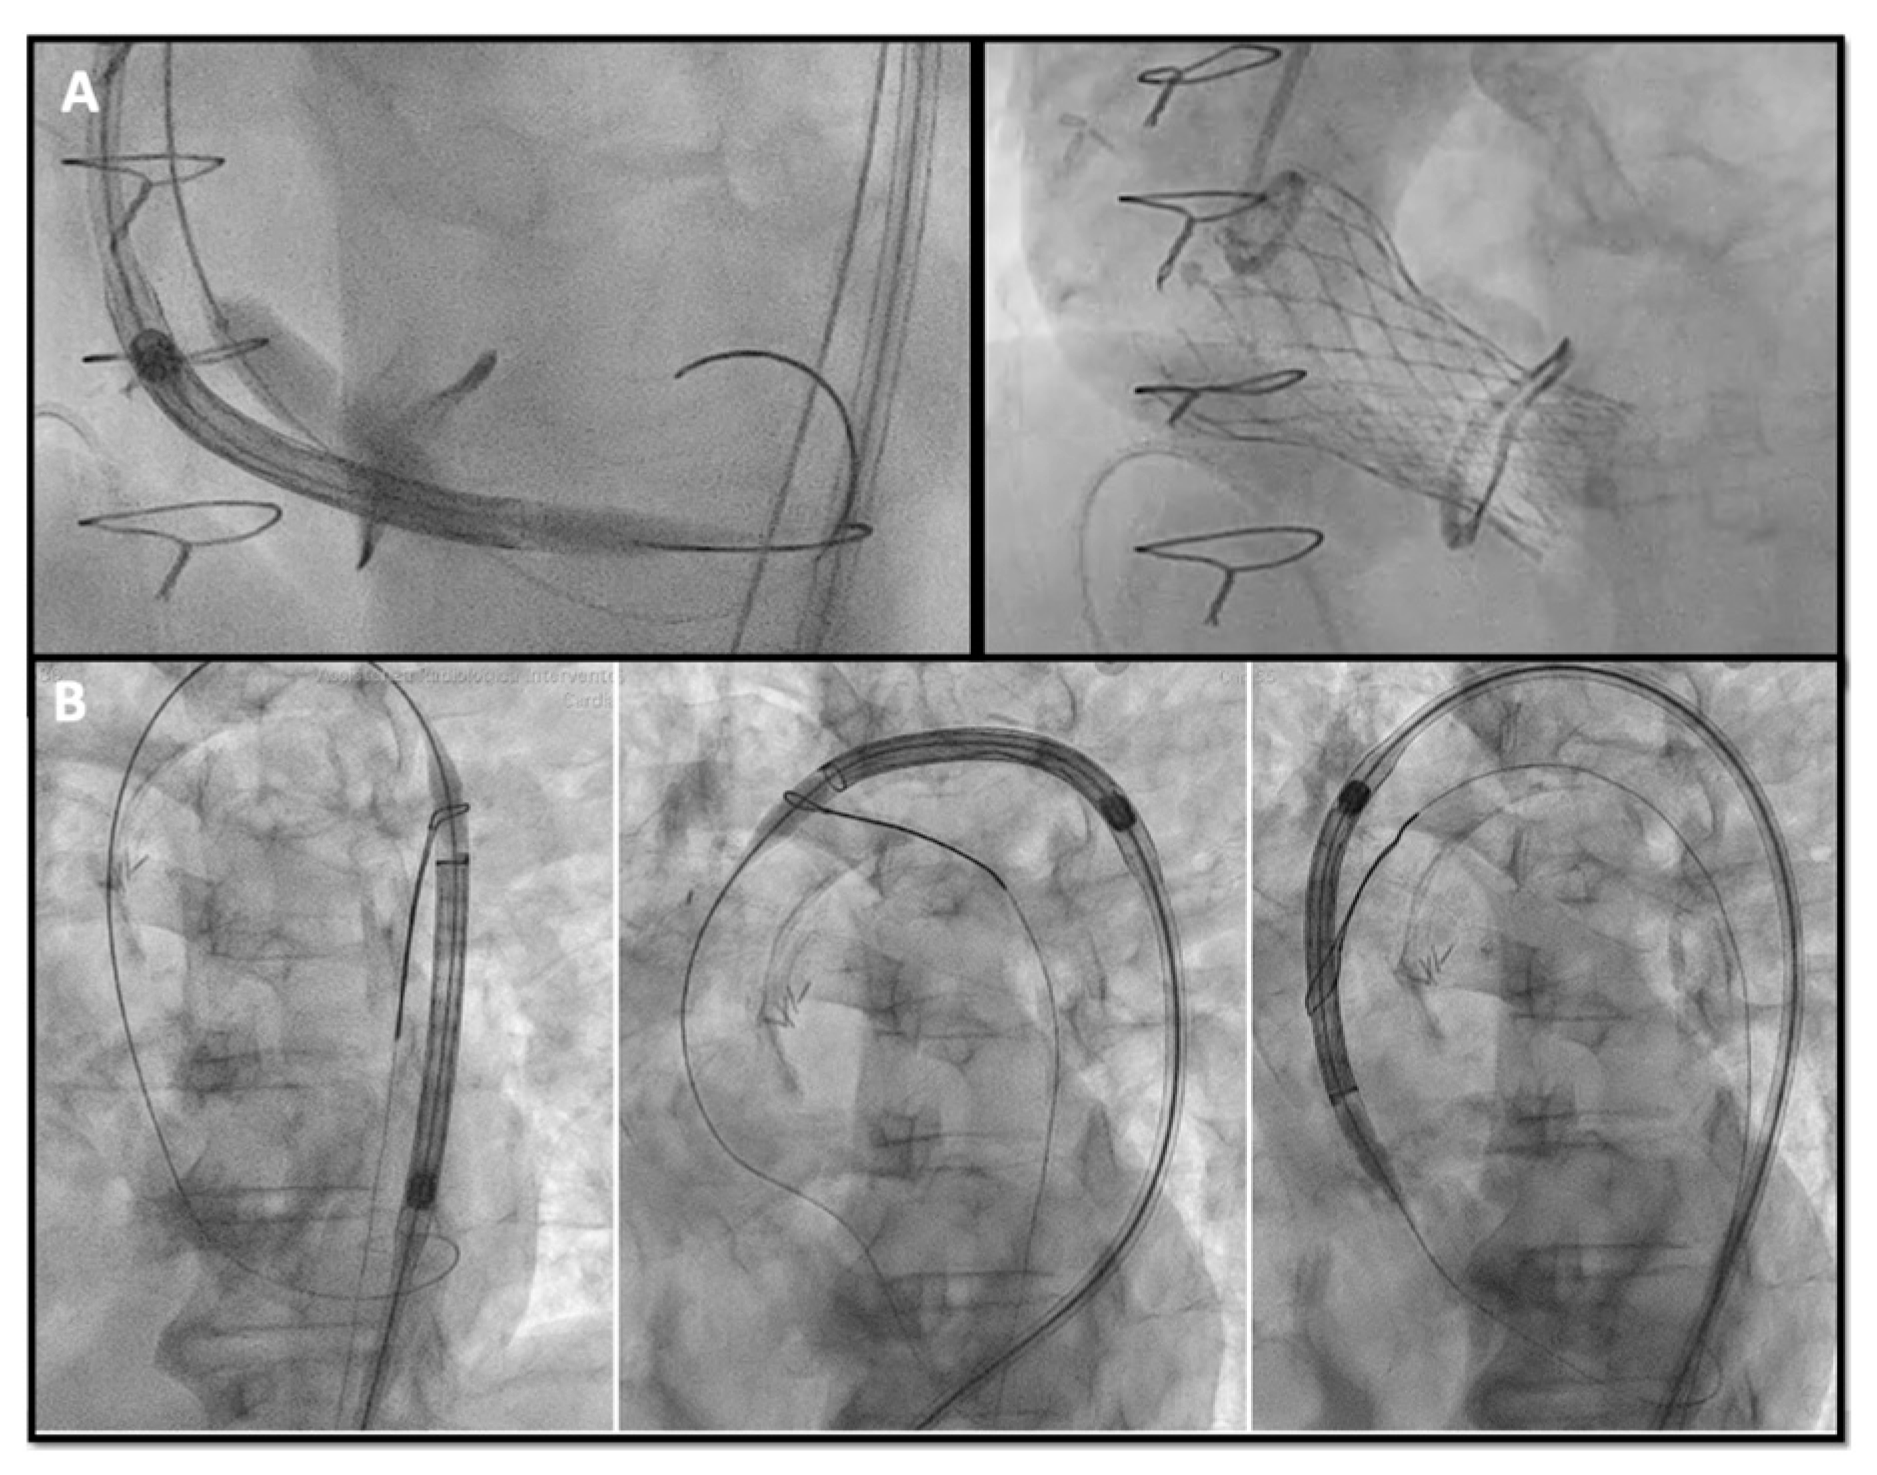

Sometimes advancing the THV in the SHV can be challenging, especially when the SHV is stenotic. Different techniques and maneuvers to facilitate advancing the THV have been described such as: (A) the “buddy wire technique”, placing two safari wires in the LV to give more support to the advancing device; (B) the “buddy balloon technique” in case of calcific or tortuous segment, if a crystal balloon is used as a buddy to provide taper to the distal end of the delivery system and facilitate crossing; (C) the “snare technique” also described as the chaperone technique [35], when a snare is inserted through the contralateral femoral artery capturing the safari wire to achieve better alignment of the delivery system within the SHV (Figure 5).

Figure 5.

(A) buddy-balloon technique with VACS II 16 mm balloon inflation parallel to the Corevalve delivery to perform ViV in a Sorin Mitroflow 23 mm; (B) transfemoral TAVR with snare technique in a severe calcific native aortic valve stenosis VIV: valve-in-valve; TAVR: transcatheter aortic valve replacement.